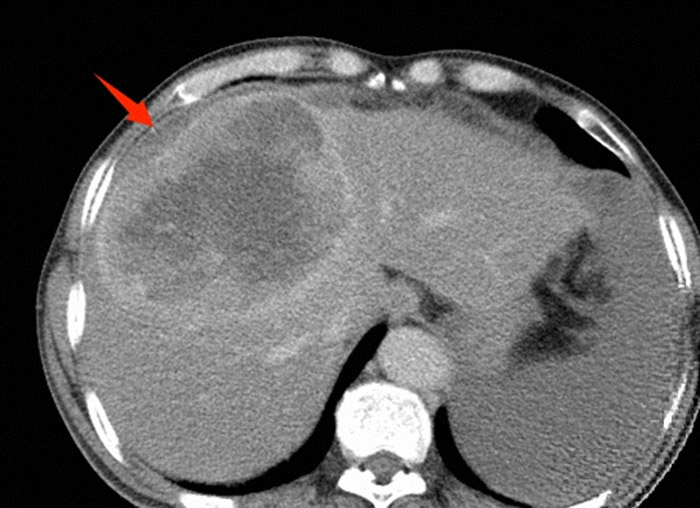

肝脏肿瘤破裂造成腹腔内出血

急诊检查结果让所有人都捏了把汗:血压最低跌至55/30mmHg,远低于正常标准;血红蛋白仅85g/L;腹部CT清晰显示肝癌病灶破裂,伴有大量出血。诊断性腹腔穿刺抽出不凝血——这是肝癌患者最凶险的并发症之一,若不能在短时间内止血,失血性休克随时会夺走生命。

术前诊断性腹腔穿刺抽出不凝血液